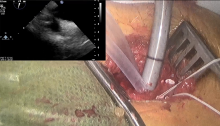

Morbidity and mortality from tricuspid regurgitation can be significant (3). However, surgery for isolated tricuspid valve regurgitation is still believed to be under-performed compared to the number of patients diagnosed. This rarity exists despite the clear guidelines to intervene in cases of severe symptomatic tricuspid regurgitation (4). The main reason for this under-performance is the reported high mortality following conventional sternotomy (5). Also, referral for surgery is often delayed until patients develop intractable right-sided heart failure. Recently, a few centers reported endoscopic minimal access tricuspid surgery with better results compared to standard sternotomy (6). In this video, the authors present a single-center experience with this type of surgery and seek to promote more surgical treatment for tricuspid valve pathologies.